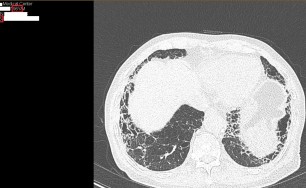

엑스레이를 가지고 왔는데 오른쪽 부비동에서 축농증 소견이 보임

천문동,포공영,백작약,신이,유근피등 25일 치료 후 경과 확인을 위해 엑스레이를 다시 찍어 보니 축농증이 많이 개선된 것이 확인됨

치료전 영상의학과 소견

치료후 영상의학과 소견